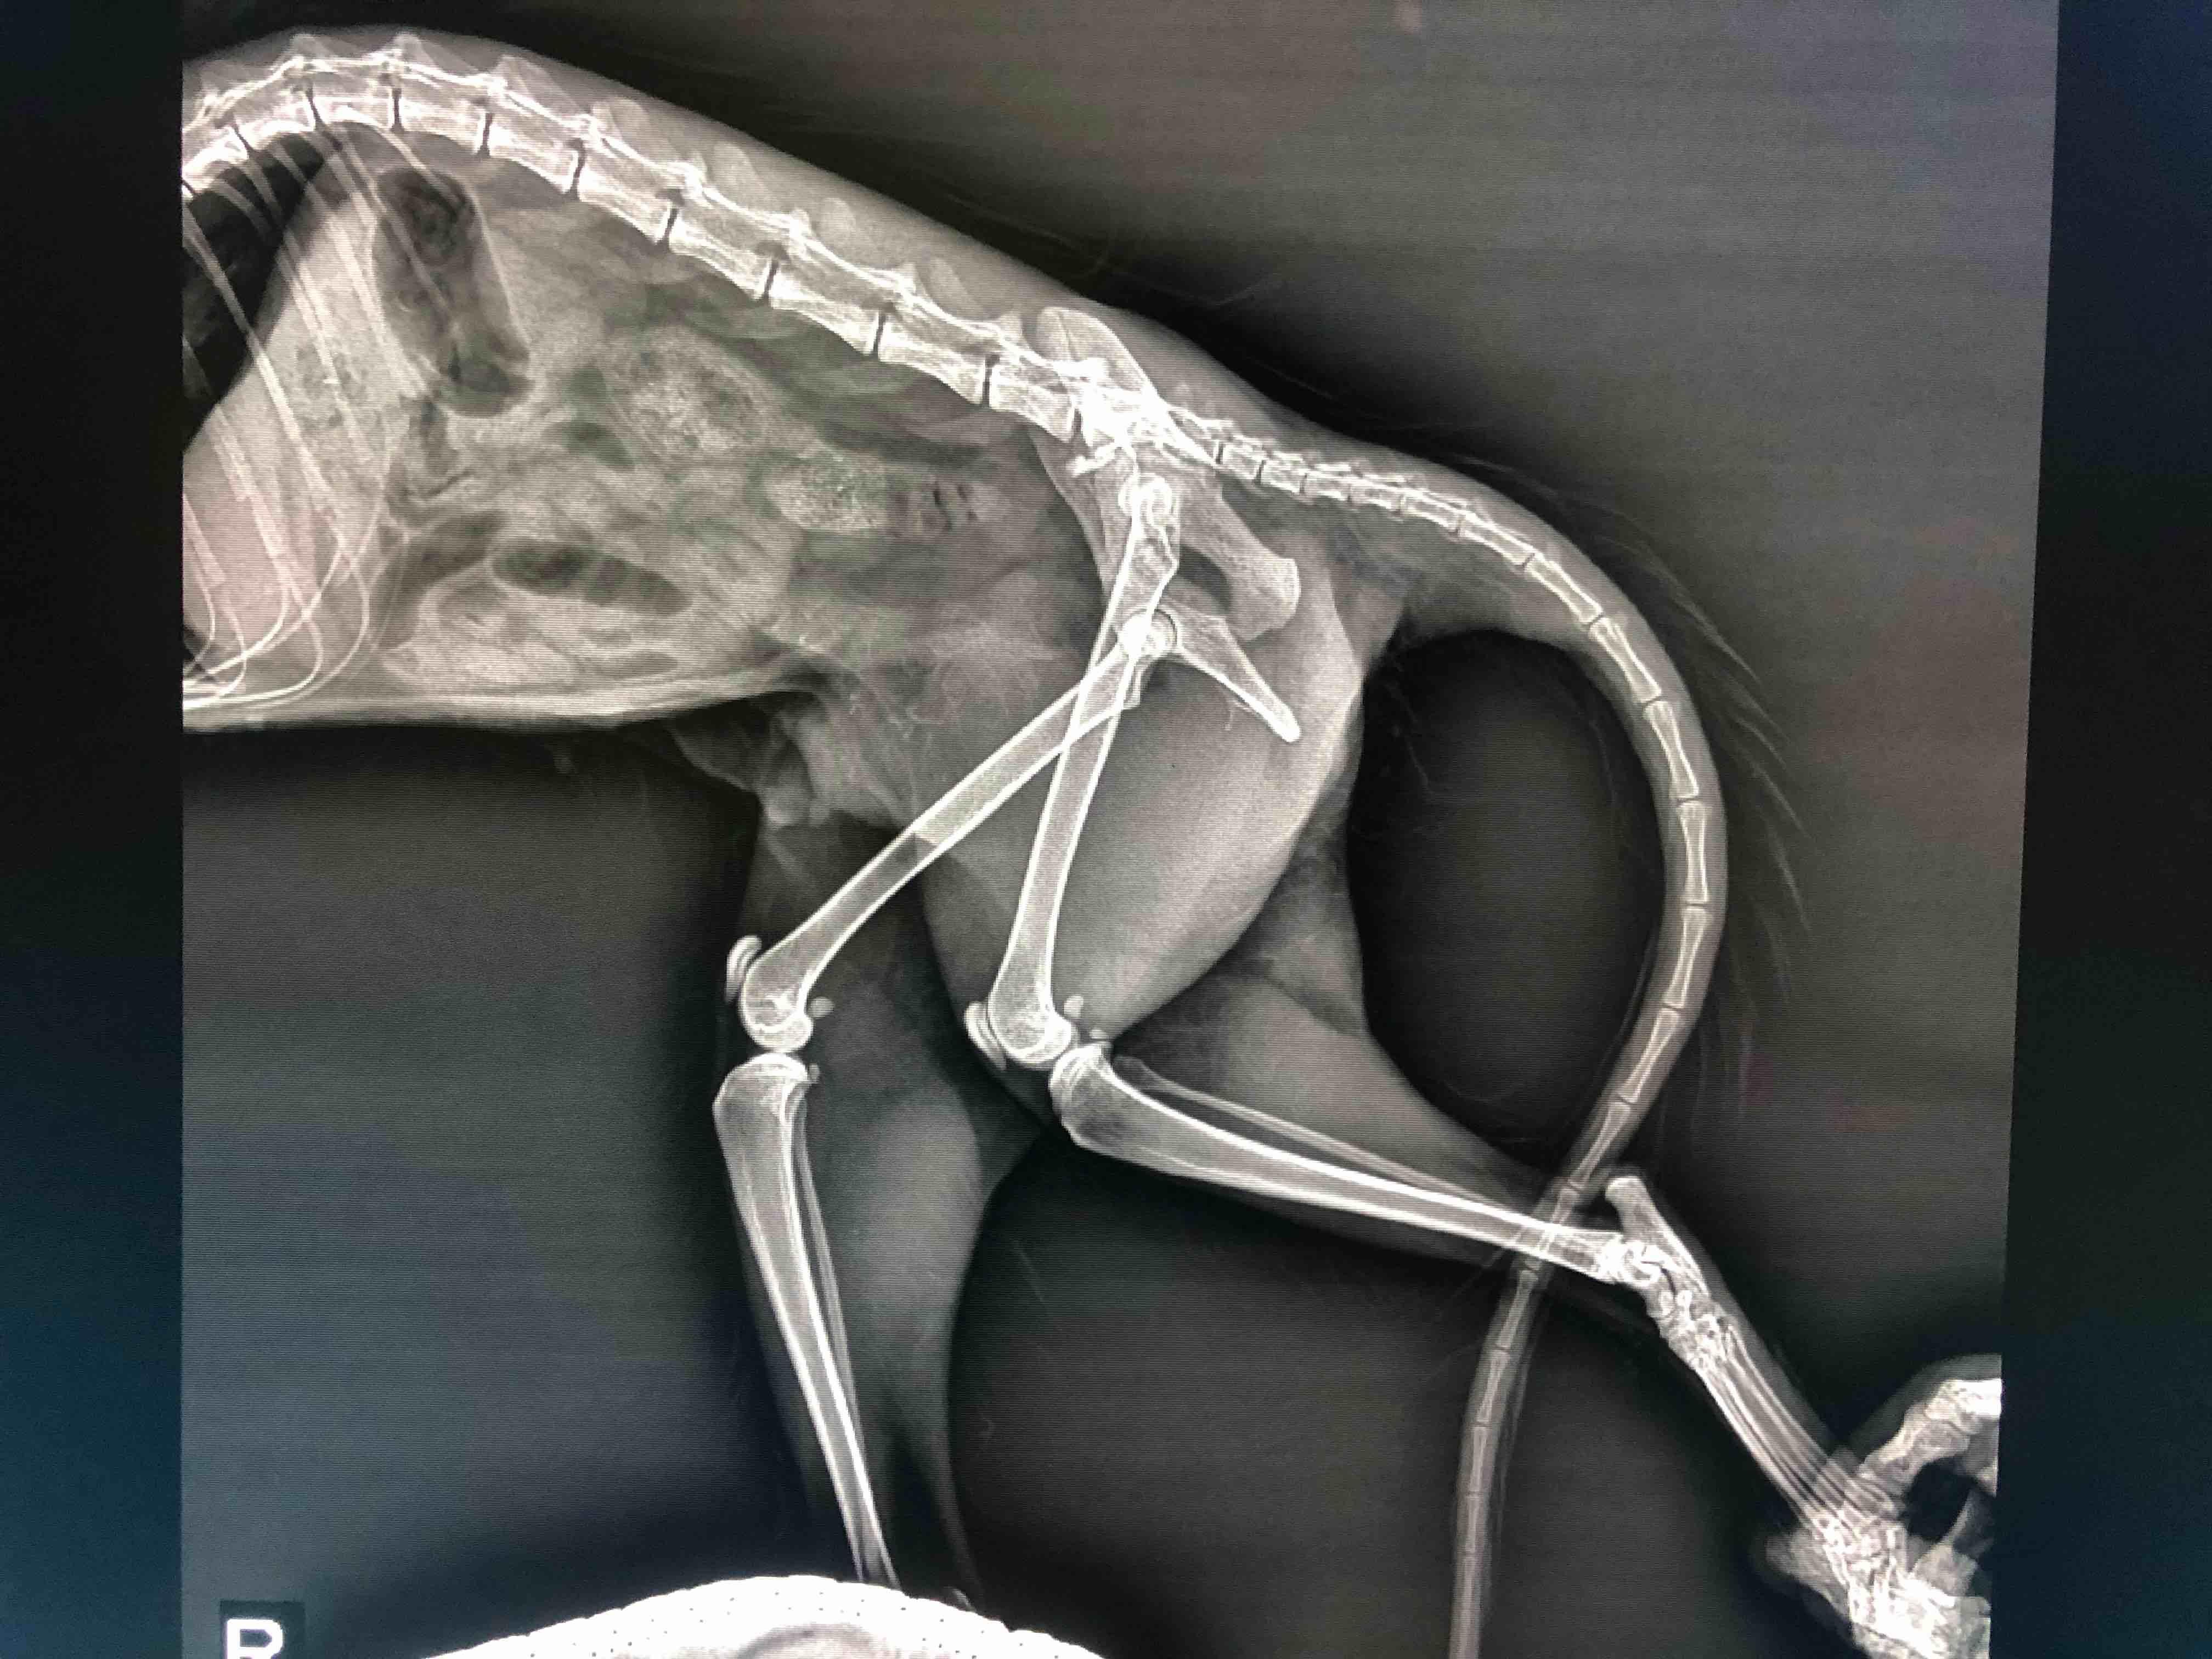

Pet's info: Cat | Mixed Breed | Female | unspayed | 11 months and 30 days old | 5 lbs

I got a cat on street broke her pelvis, I wonder if she can heal on her own or we have to do the operation. With infection and anemia, still stay in hospital.

Poor girl. This is severe break and the pieces are not at all aligned. Unfortunately because the two bones are not aligned properly to heal back together naturally, this likely needs surgical correction. Poor kitty. : ( I recommend discussing with the vet about surgery for this poor kitty to help align the bones. I am not an orthopedic surgeon however, so a consult is needed to discuss if this particular break is repairable surgically or if there are other things that need to be done. Best wishes with your stray kitty Wen. Take care!